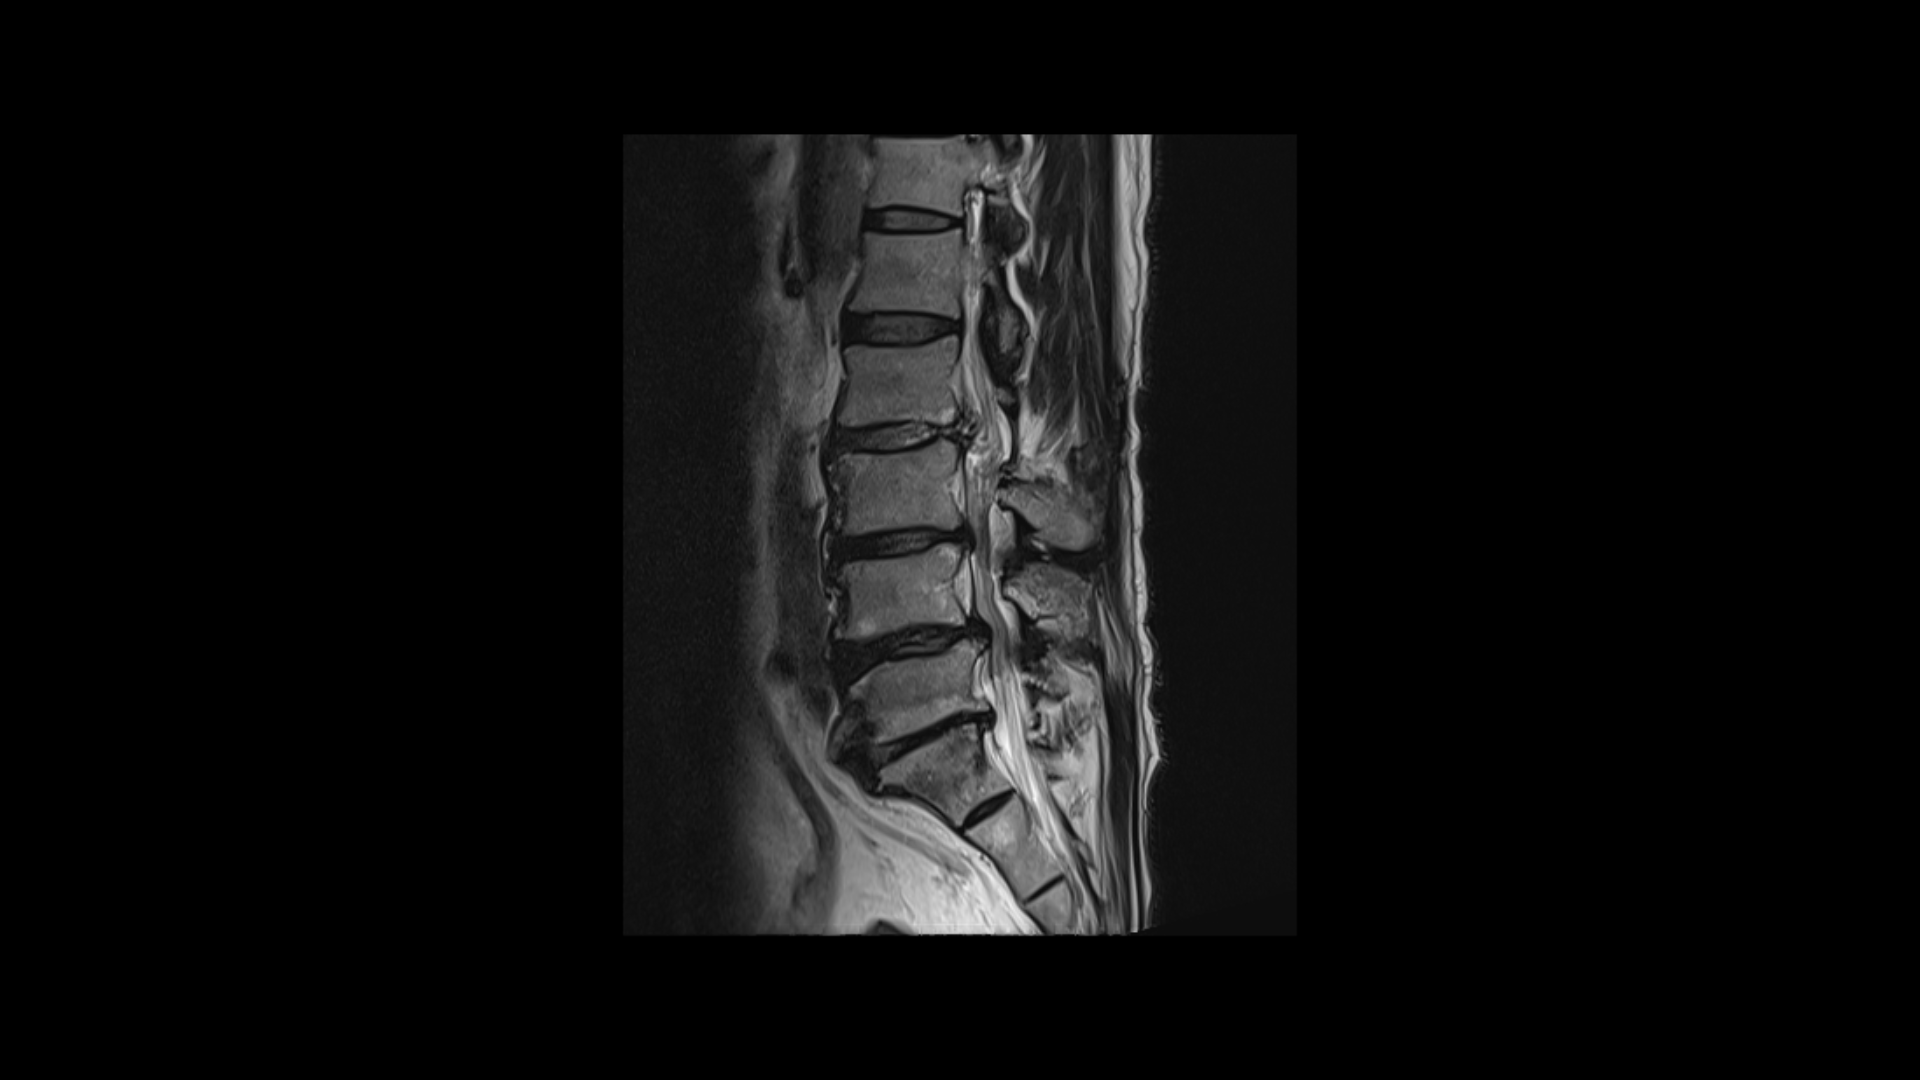

이분 MRI를 보면 네 마디에 퇴행성 디스크가 있고

두 마디에 중심성 협착이 있고

좌우로 나가는 신경구멍이 디스크와 협착으로 많이 좁아져 있습니다.